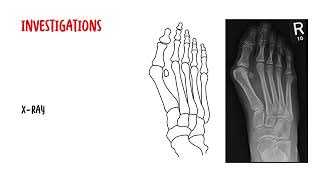

This video breaks down what viewers will learn: the mechanics behind medial deviation of the first metatarsal and lateral drift/rotation of the big toe, how toes should align during gait, and why weakened ligaments, muscle imbalance, genetics, age, and narrow/high-heeled shoes increase bunion risk. You’ll see how bunionettes (tailor’s bunions) differ, what to expect on clinical exam and weight-bearing X-rays, and the diagnostic threshold (typically >15°).